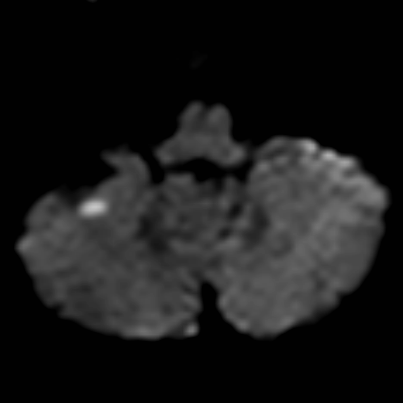

相逢就是缘,有求必全力以赴。立即进行全面评估,CTA和MRI发现颅内多发脑梗塞,脑干为重,双侧椎动脉颅内段基本看不到了,而进一步的DSA造影更为糟糕,左侧椎动脉的颅内颅外段直接全程完全闭塞,右侧颅外剩下一个小尾巴在血液中摇摇欲坠……,诺大的后循环仅仅靠纤细的后交通动脉从前循环借点血液过来,勉强续命,仅仅靠这点前循环的救急,可谓“杯水车薪”,不是“长久之计”,于是决定开通右侧闭塞的椎动脉(颅内+颅外,主要集中在V3+V4段)。